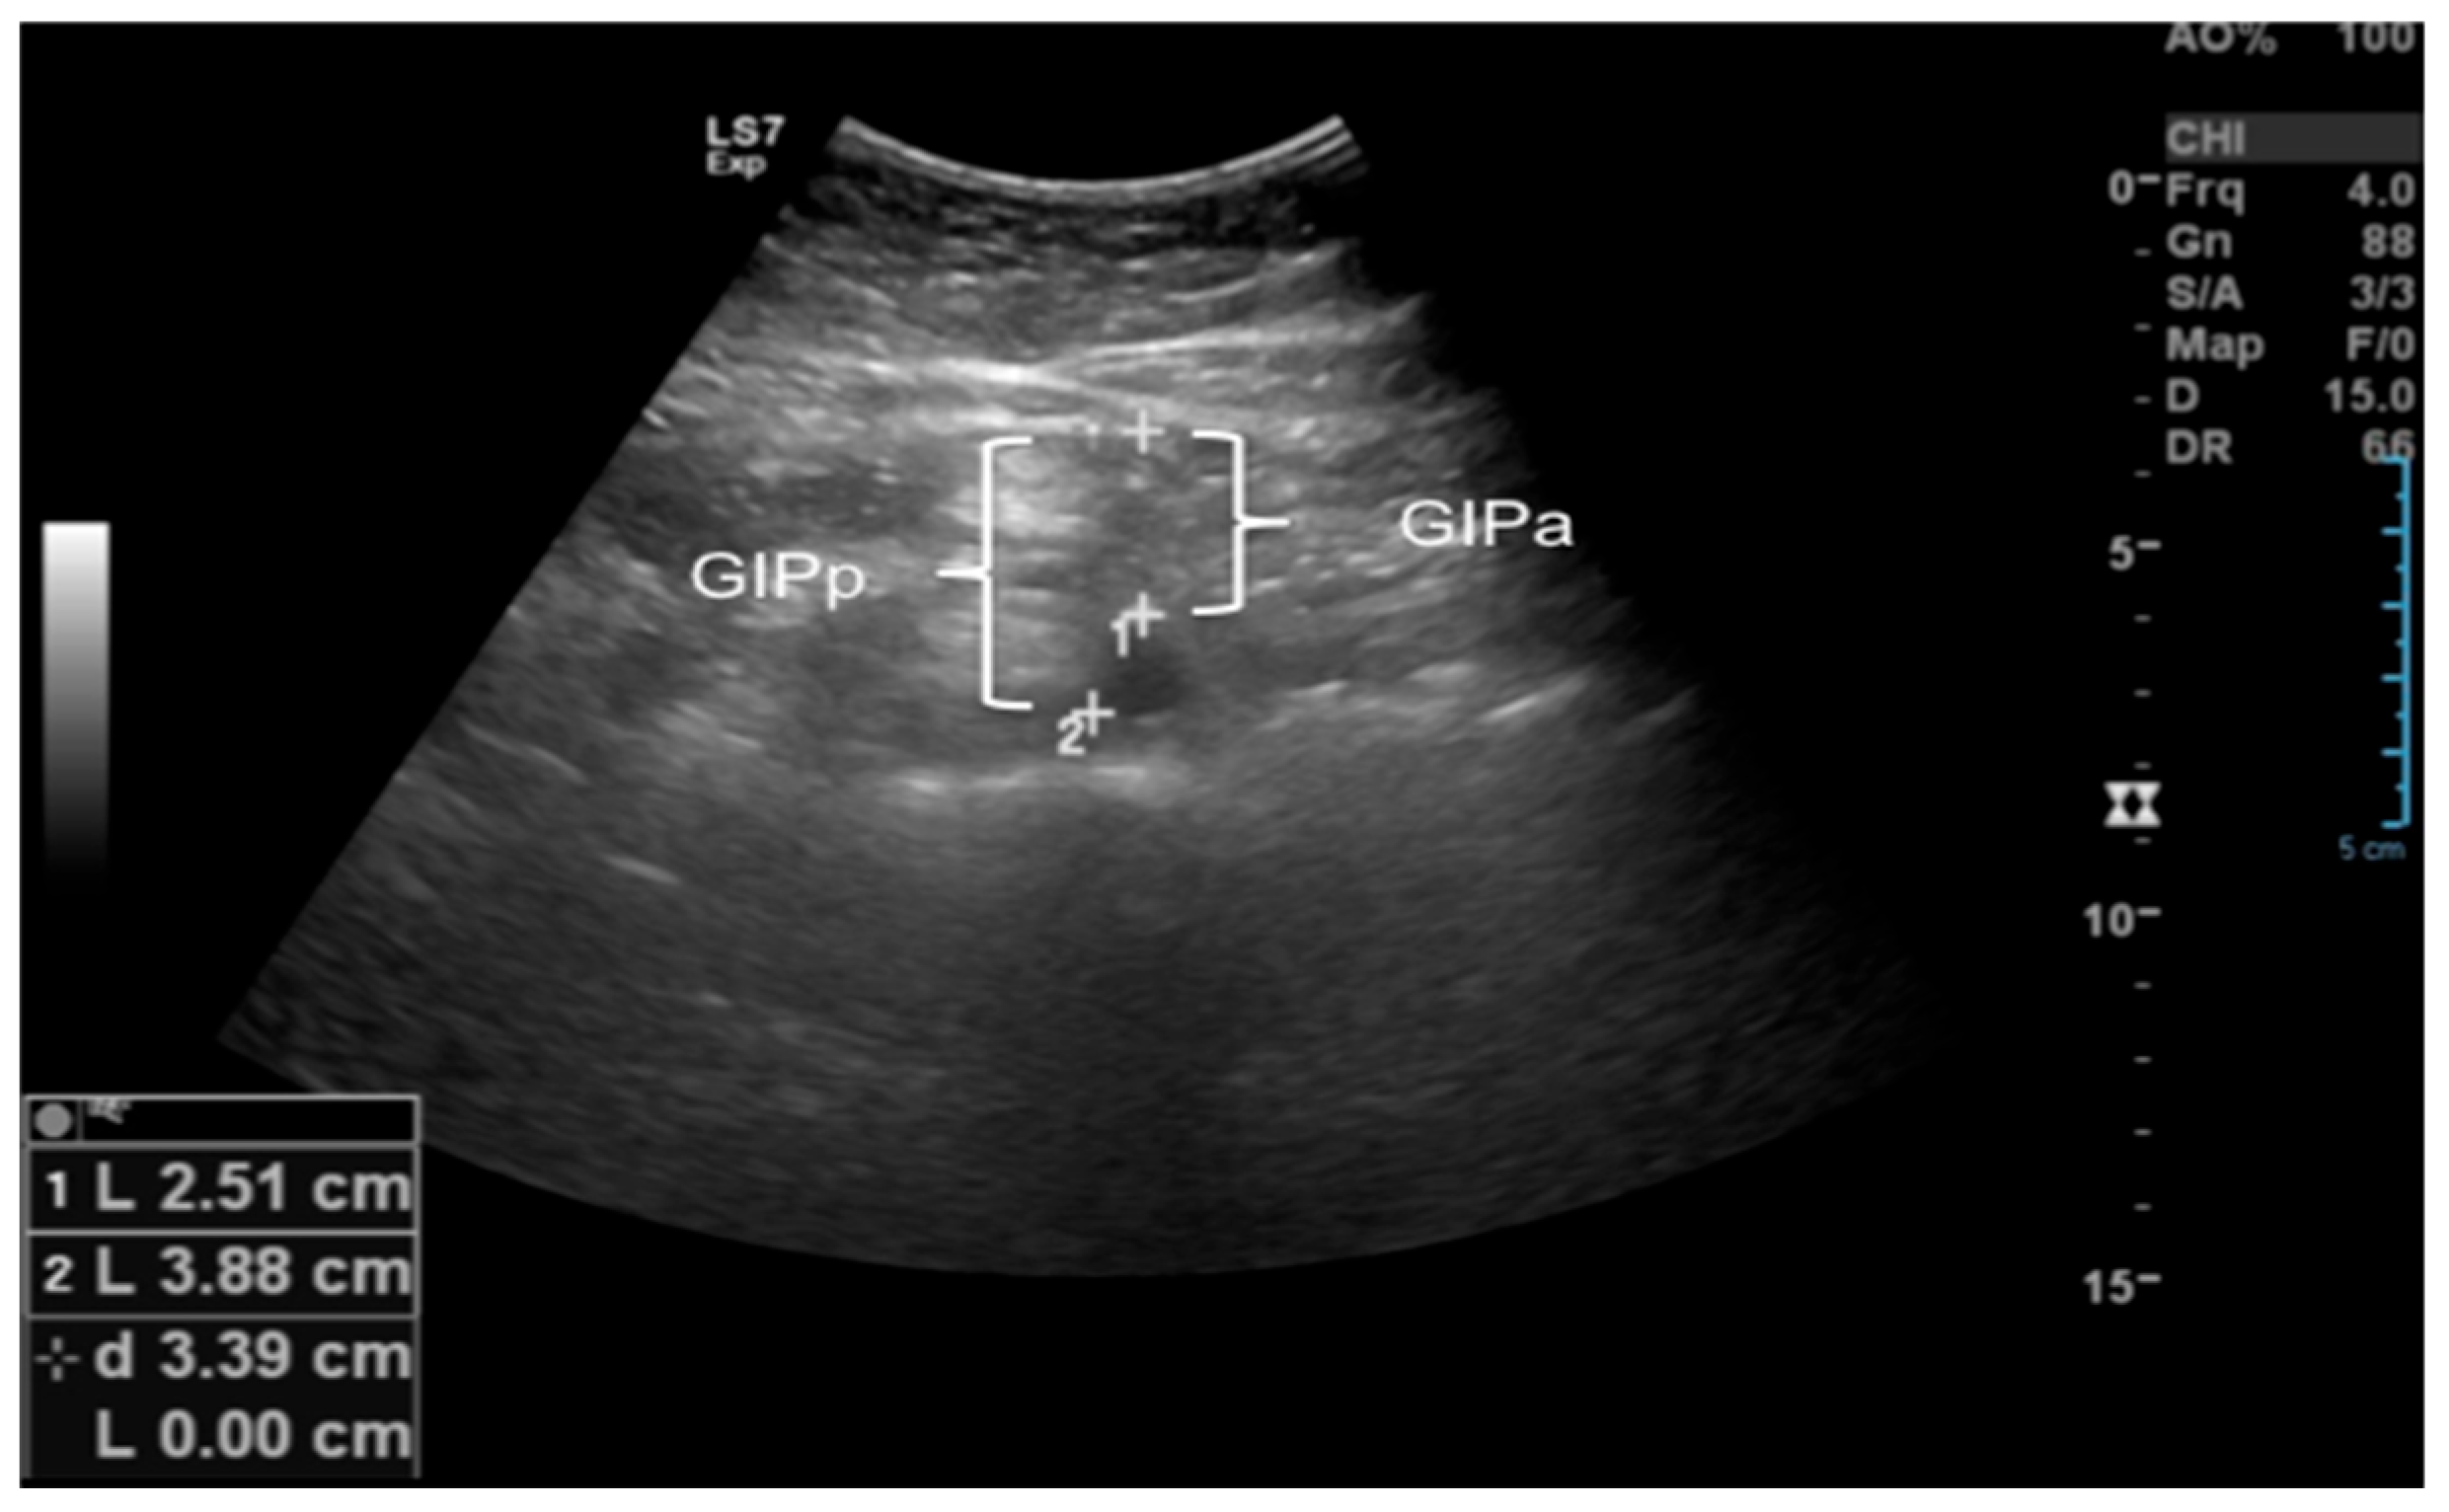

2.2.2. Ultrasound of Subcutaneous and Intra-Abdominal Fat

| Intra-peritoneal fat (IPFa—anterior wall of the aorta, cm) | 3.41 ± 0.66 | 3.66 ± 0.96 | 4.41 ± 1.17 | 0.003 *& |

| Intraperitoneal fat (IPFp—posterior wall of aorta, cm) | 4.21 ± 0.73 | 4.50 ± 1.17 | 5.33 ± 1.22 | 0.028 * |

| Intraperitoneal fat (IPF—lesser omentum, cm) | 0.81 ± 0.15 | 0.94 ± 0.24 | 1.15 ± 0.33 | 0.001 *& |